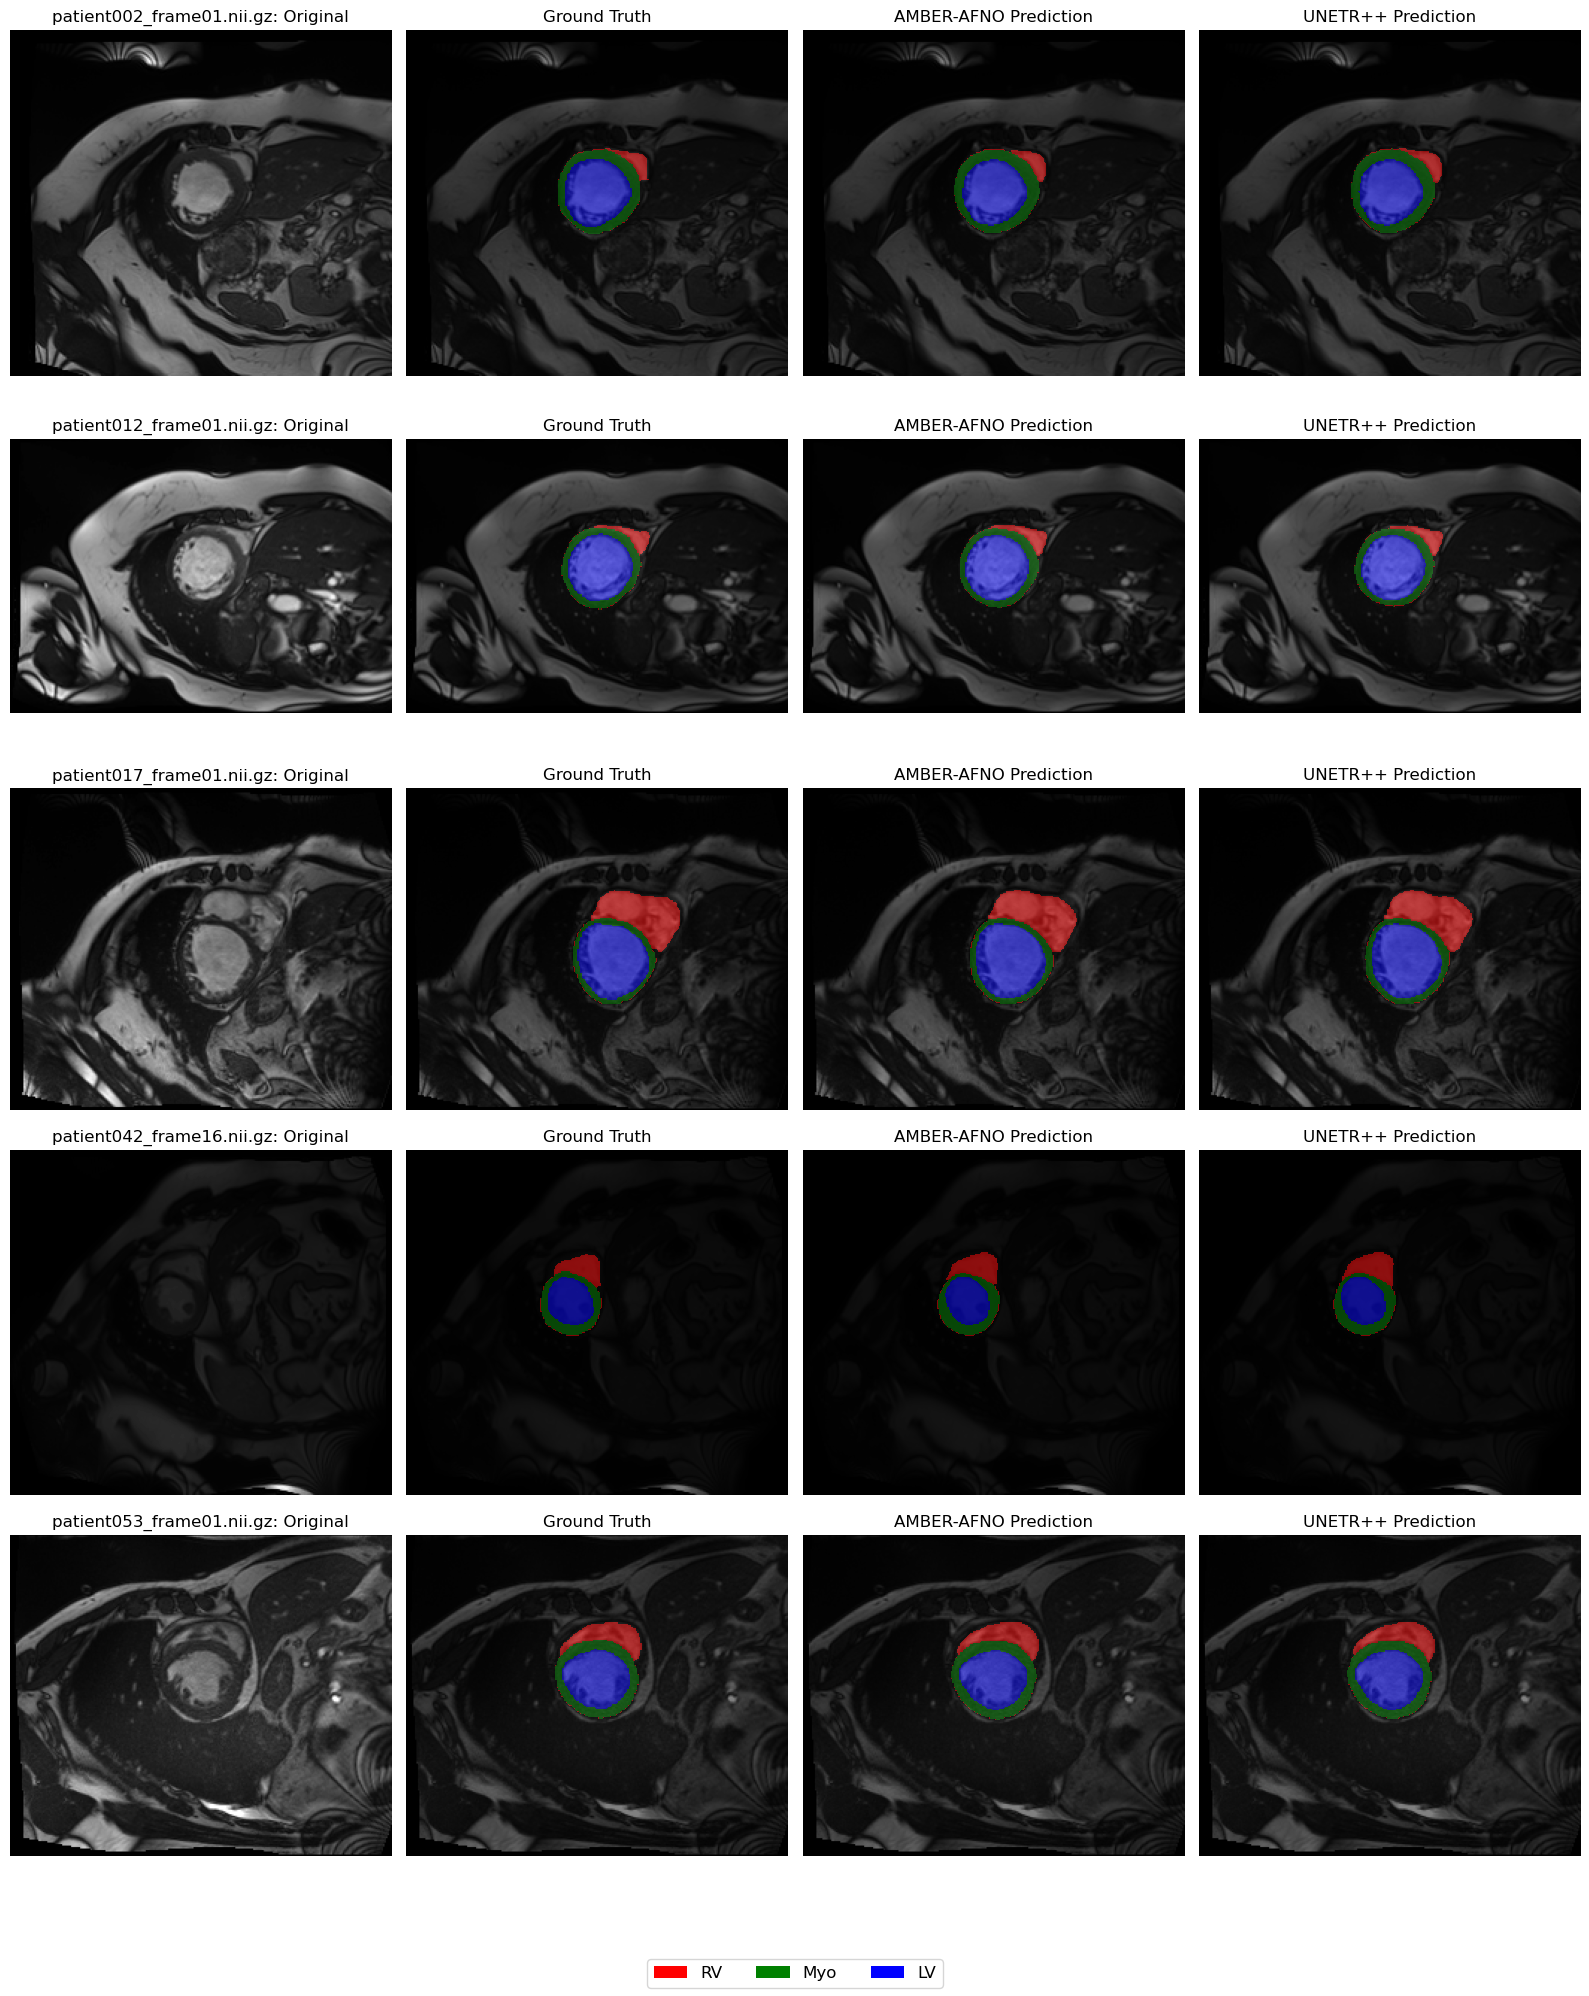

Refer to caption

Figure 4: Visual Comparison of AMBER-AFNO and UNETR++ Model on ACDC Dataset

Tab. 2 and 3 show that AMBER–AFNO achieves the highest overall Dice score in the ACDC validation set (92. 85%), outperforming UNETR ++ (92. 83%) while using fewer than half of its parameters. The proposed model delivers the best myocardium segmentation (90.74%) and ranks second on both the right-ventricle (91.60%) and left-ventricle (96.21%) classes, demonstrating balanced accuracy across all cardiac structures. These results confirm that the AFNO encoder, combined with a lightweight SegFormer-style decoder, can match, or even surpass, state-of-the-art baselines in ACDC with substantially reduced computational demands.

The ACDC dataset (Bernard et al., 2018) consists of 3D cardiac MRI images with multi-class annotations. A total of 200 labeled samples were used, split into 160 for training and 40 for testing. The annotated classes include the right ventricle (RV), myocardium (MYO), and left ventricle (LV). In this study, the Dice Similarity Coefficient (DSC) was used as the evaluation metric for model comparison.